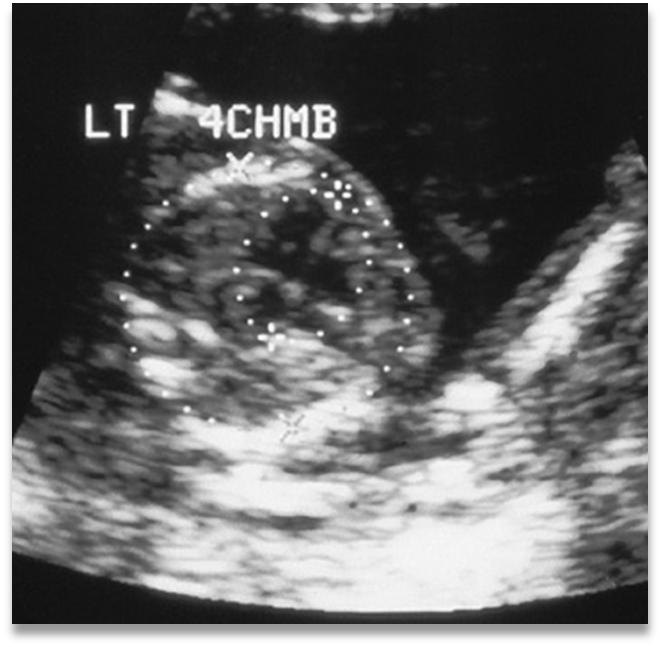

What view is this?

outflow tract

4 chamber view

Normal 4 chamber view

Identify structures of the heart